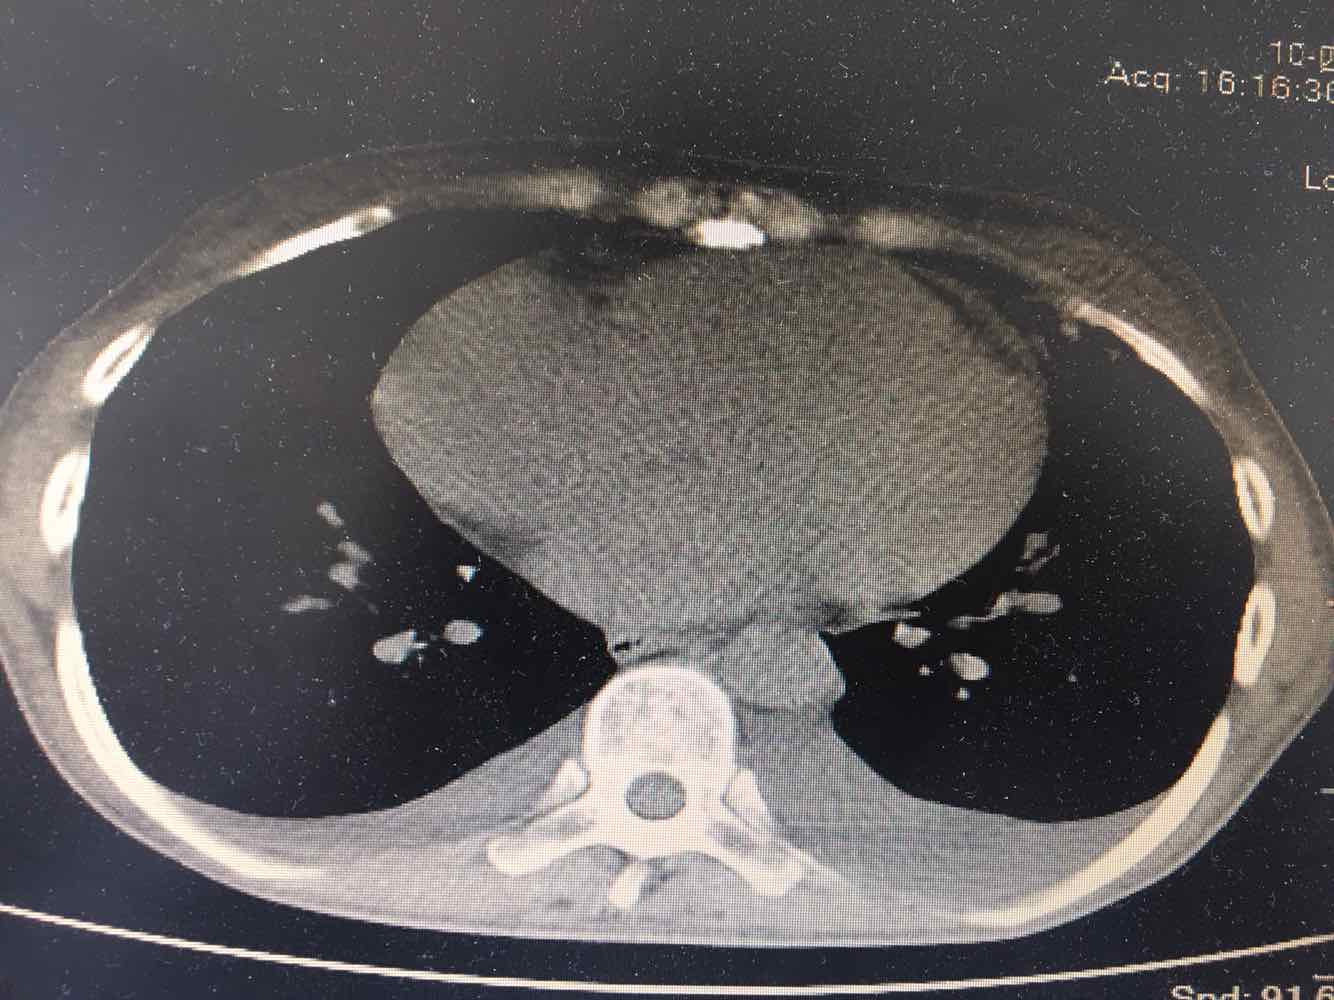

女,51岁,支气管扩张病史多年。慢性咳嗽咳痰喘息30年,加重1个月,无发热,气短为主,痰液不多,上腹不适,少尿。双肺干湿罗音。